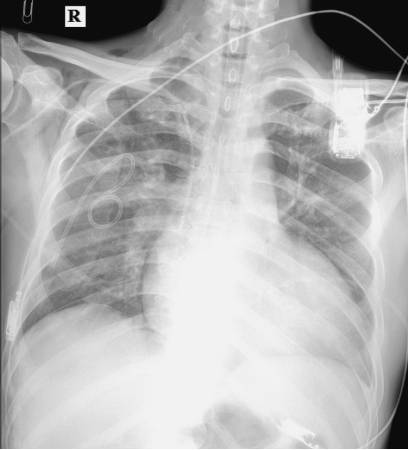

2015年9月22日